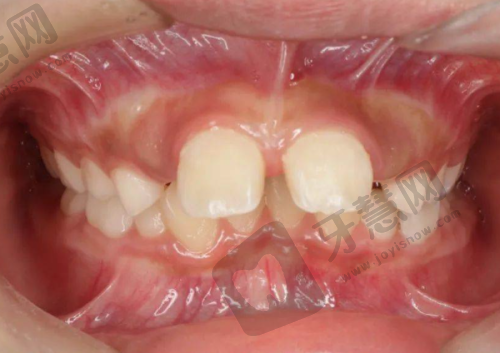

首先来看吸附性义齿方面。这里设备非常精良,医院引进了高端的口腔诊疗设备,像口腔领面X - CT机、牙片机等。这些设备可不容小觑,它们能够严谨测量患者的口腔数据,为制作精细的吸附性义齿提供了有力保护。医生团队也十分专精,他们具备扎实的口腔知识和丰富的临床经验,能根据患者具体情况制定个性化治疗方案。而且医院注重与患者的沟通与交流,充分了解患者需求和期望,提供贴心服务。在患者佩戴吸附性义齿的过程中,还提供完善的售后服务,确保一旦遇到问题能及时得到解决。

再说说种植牙。医院采用德国数字化Sirona CBCT设备和3shape口扫设备,实现了种植牙手术的数字化和精细化。医生可以通过三维口腔结构图像的展示,从任意角度观察分析患者病例,为种植牙手术提供精细的数据支持。这大大缩短了手术时间和周期,提高了患者的舒适度。医疗团队能熟练掌握各种种植牙技术,同样可以根据患者的具体情况制定个性化治疗方案。